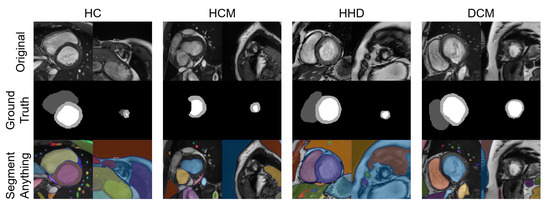

A total of eight images were tested with the SAM “every” mode. The segmentation results are shown together with the manual segmentations in Figure 10. The results of the SAM showed an acceptable performance on the basal slices; however, for the apical slices, none of the four apical slices showed acceptable results.

Figure 10. Eight images with manual segmentations and SAM segmentations. For each disease type, we selected an apical slice and a basal slice.

With the advent of the segment anything model (SAM) [31], we chose some of our images as inputs and tested their segmentation ability with the “every” mode https://segment-anything.com/demo (accessed on 10 April 2023).

4.3. QC with the Mature Segmentation Model

In contrast to diagnostic applications, a QC system should prioritize the detection of bad-quality segmentations, rather than improving the classification accuracy. As a result, we chose the NDR as our primary criterion for the classification evaluation. Additionally, we observed that deep learning segmentation models for cardiac segmentation are currently well-developed. The reported average DSC is 0.85–0.97 for the ACDC-2017 dataset and M&M challenge dataset with various DL model structures [3,33,34,35]. As previously mentioned, mal-segmentations at the slice level are primarily distributed in the apical or basal regions of the heart. However, these low-quality segmentations have little effect on the 3D DSC prediction. This partially explains why the 3D DSC is higher than the 2D DSC (refer to Table 4). However, it is important to note that the absence of apical or basal slice segmentations can significantly impact the 3D radiomics features, such as the maximal long axis length, particularly in the shape feature group. This phenomenon was also observed in our experiment (Supplementary Tables S7 and S8). Meanwhile, although coarse borders may not significantly impact the 2D or 3D DSC, certain radiomics features are sensitive to edges, as demonstrated in previous studies [36,37,38]. The characteristics exhibited by radiomics-based quality control systems provide a new evaluation perspective compared to previous methods. This makes radiomics an ideal method for automatic segmentation evaluation and quality control. As shown in Figure 10, the segmentation of apical slices remains challenging, which is why a quality control system is necessary, even with the use of large models, such as SAM.